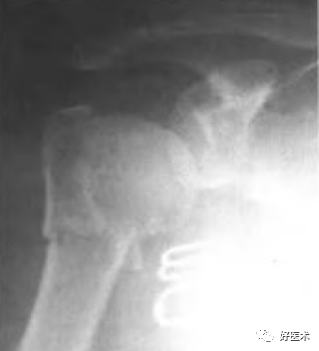

四部分骨折:

-

软组织损伤严重

血运破坏严重

肱骨头坏死率大

手术并发症多

功能恢复慢

对于60岁以上的老年病人人工肱骨头置换是手术适应征。